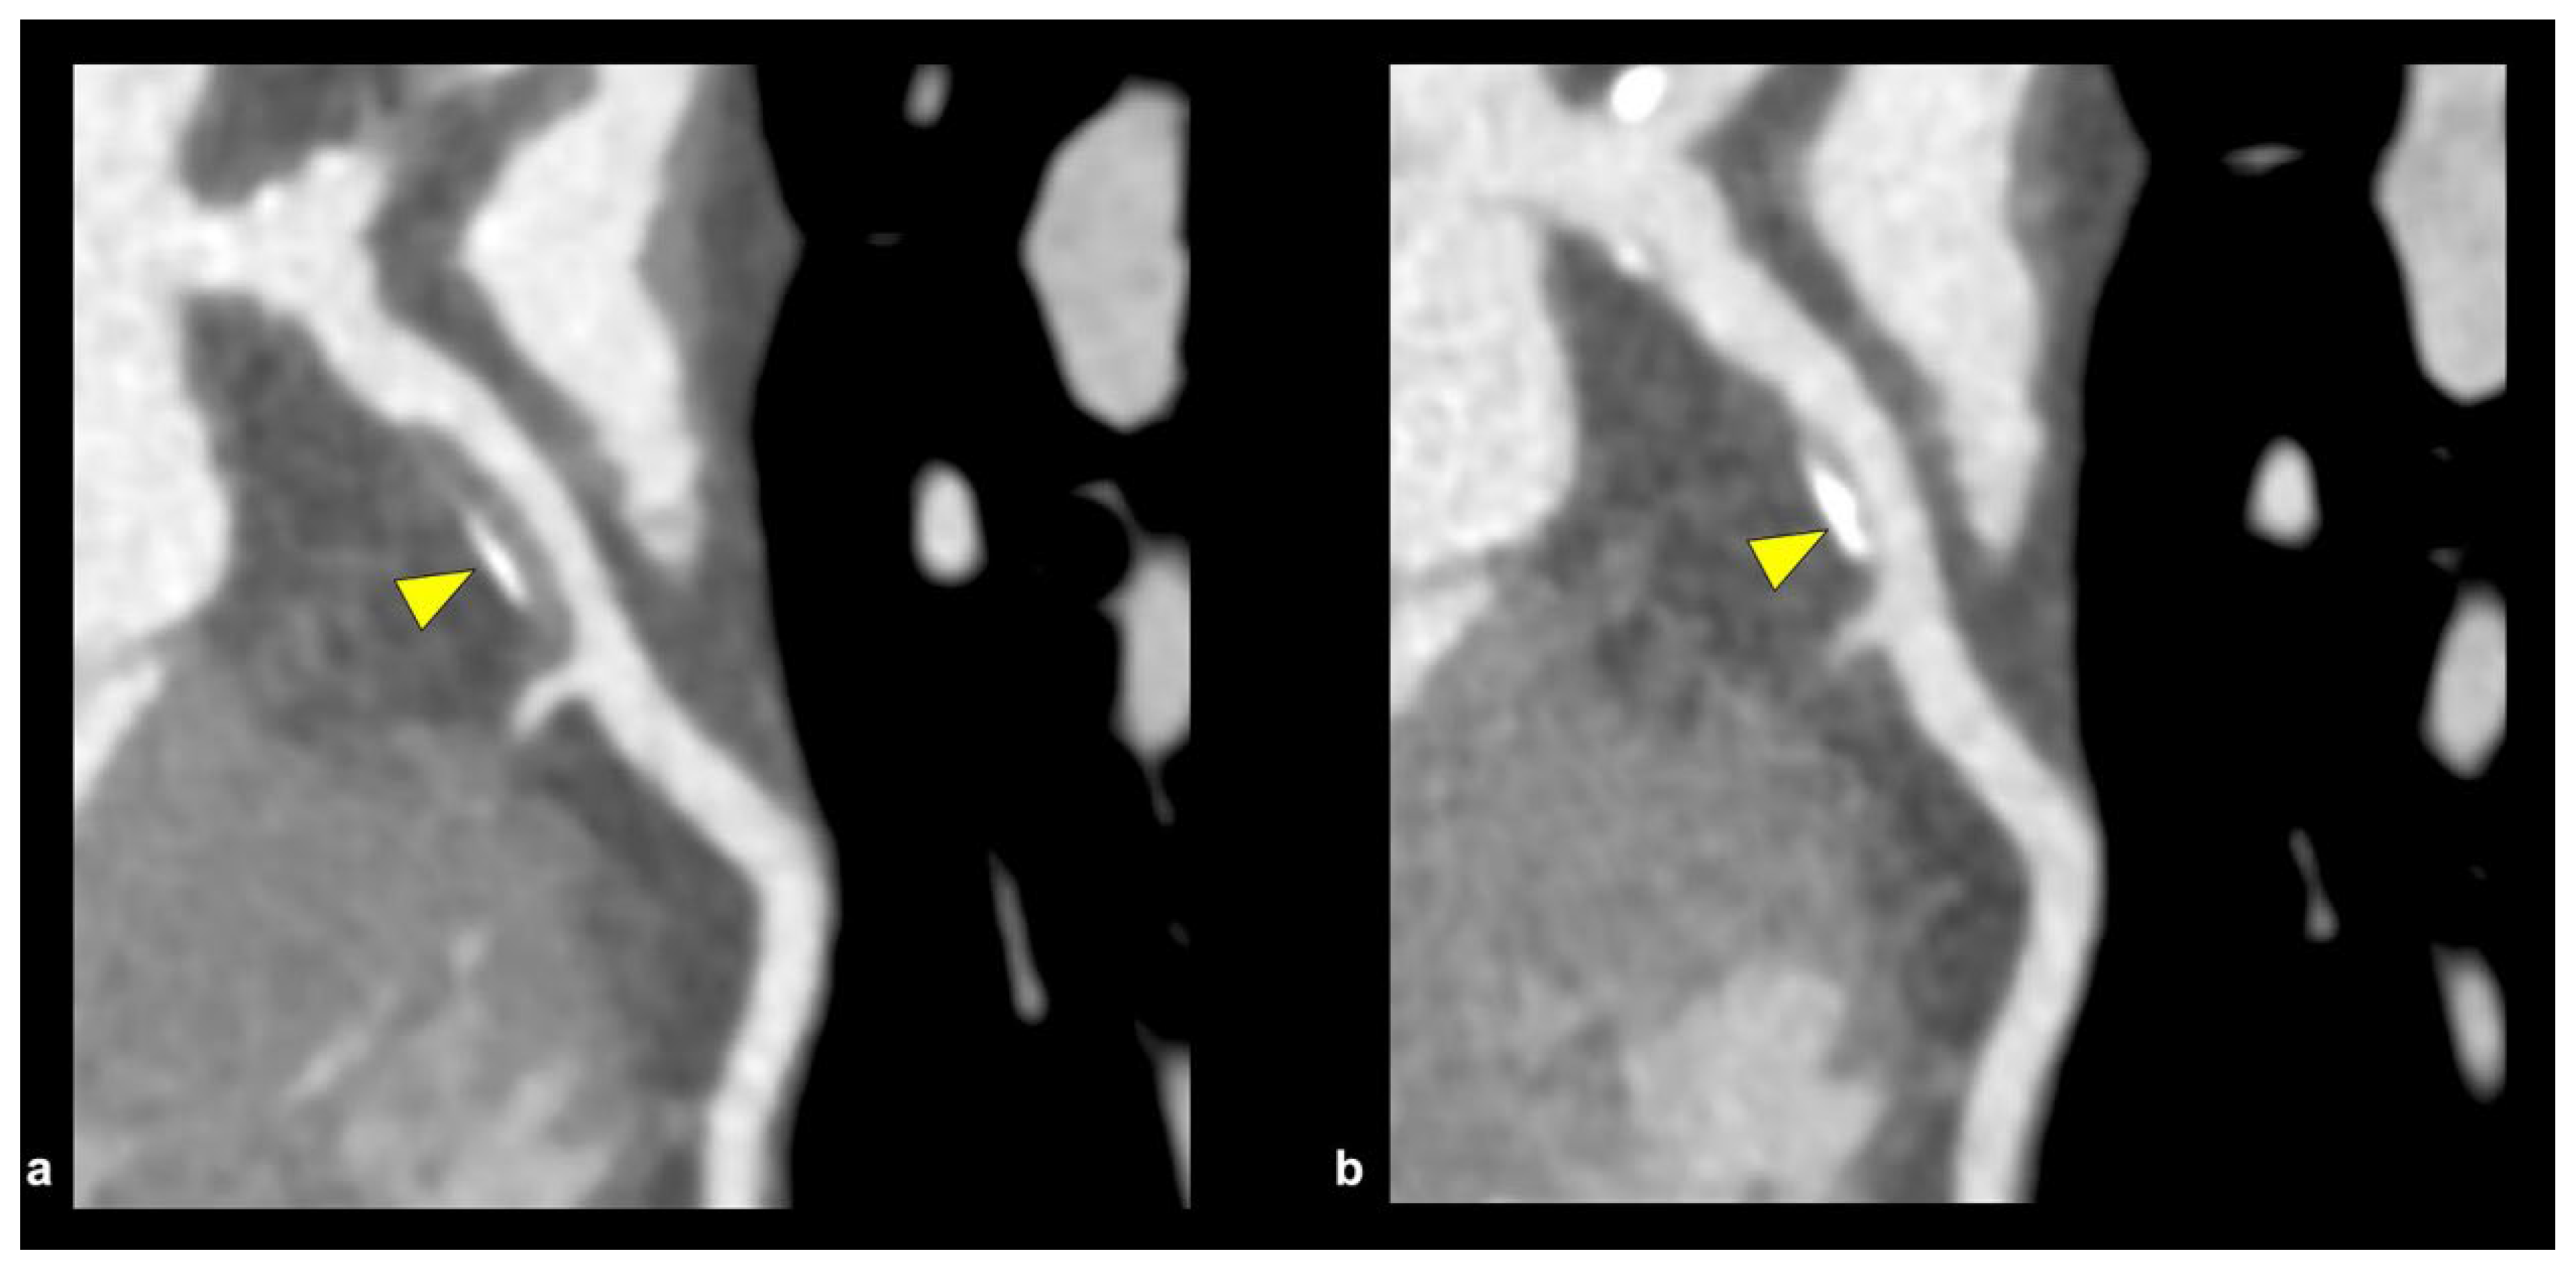

6.1. Coronary CT Angiography

Coronary CT angiography (CCTA) (Figure 10) is a non-invasive tool that provides high sensitivity and high spatial resolution. It quantifies the coronary artery calcium score (CACS) for the long-term assessment, risk stratification, and treatment of high-risk plaque features, which include positive remodeling, low attenuation, the “napkin-ring sign,” and spotty calcification [47,48]. The main culprit and high-risk lesion in ACS patients are the presence of the “spotty pattern” of calcium deposit plaques (focal calcification < 3 mm in diameter) when compared to the non-culprit calcium lesion (contiguous calcification > 3 mm in diameter), but discrepancies and inconsistencies occur when the highly dense calcium plaques (>1 K Hounsfield units on CCTA) are included [48].

Complex calcified plaques place a huge burden on the coronary arteries in such a way that partial or even complete chronic total occlusions (CTOs) of the native vessel can occur, thereby greatly reducing the overall diameter of the vessel to far below the normal hemodynamic flow it needs. “Full-moon” coronary calcification occludes the entire coronary vessel and is detected through CCTA imagery [55]. This plays an important role in detecting vascular architecture and the procedural planning needed for calcium plaque debulking. The “full-moon” calcification that was detected by CCTA was studied in two European centers, and after analysis of 1324 CTO-PCIs was performed, it was found that CTOs in association with “full-moon” calcific lesions were more commonly seen in proximal locations in coronary vessels, in addition to a high dominance in the right coronary artery [55]. CCTA has played a crucial role in being able to examine, assess, and procedurally plan complex calcium plaque, like CTO with “Full moon” morphology.